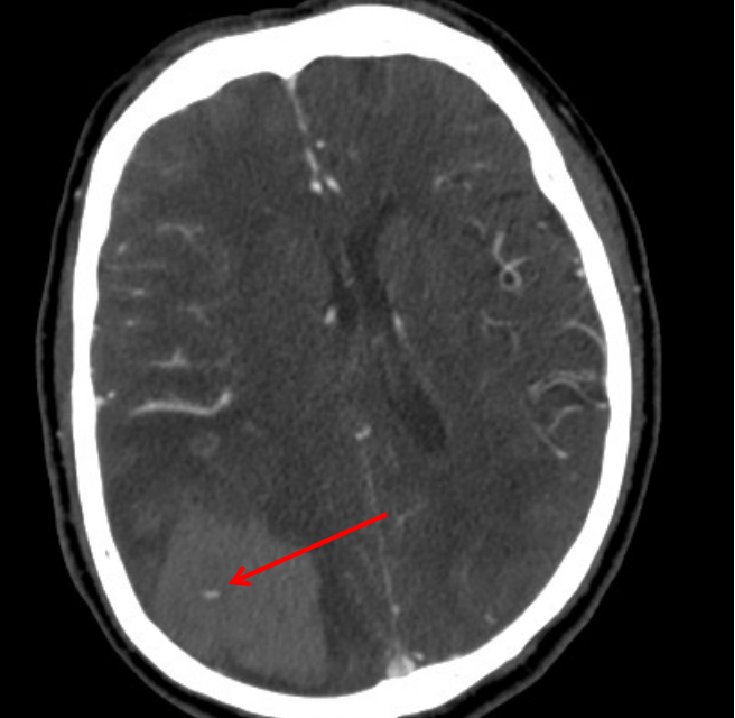

头颅CT示:右侧颞顶枕叶脑出血(78ml),内斑点、小片状持续强化灶,活动性出血?血管畸形?

术前CT

血肿内疑似有血管畸形